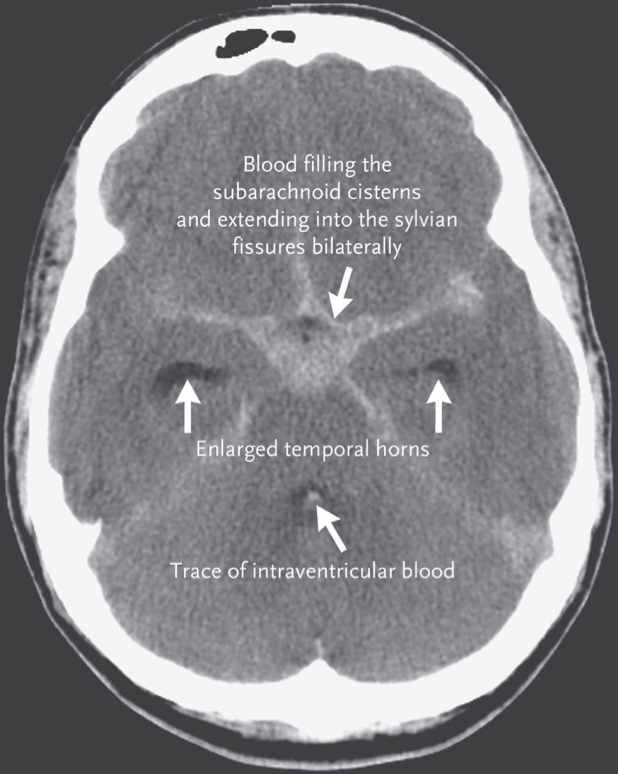

Subarachnoid Haemorrhage

Aetiology & Pathogenesis

- Rupture of berry aneurysm in Circle of Willis

- Common sites: MCA > ACA > PCA

- Blood enters the subarachnoid space, mixing with CSF

- May be precipitated by hypertension

Morphology

- Blood in sulci and basal cisterns

- Can appear in ventricles if severe

Investigations

- CT Head: Blood in sulci and fissures

- Lumbar puncture: Xanthochromia (if CT negative)

- CT Angiography: To identify aneurysm